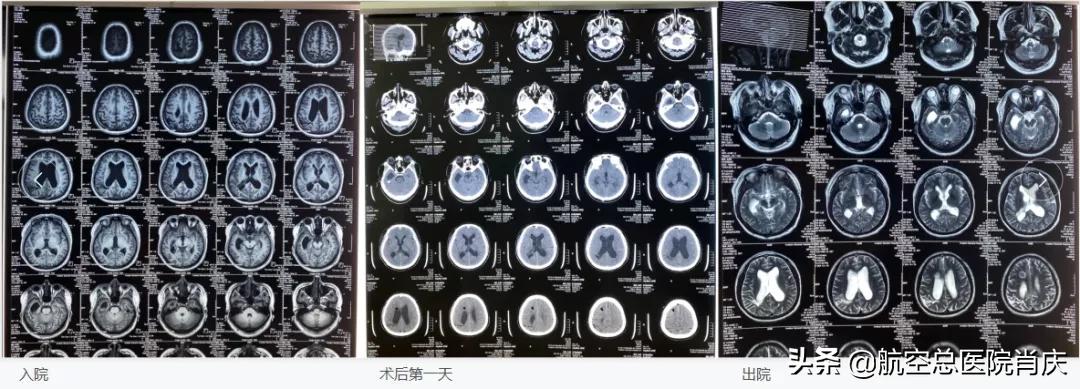

肖庆主任在门诊得知马先生的病情后,凭借经验感觉事情没有表面看起来的那么简单,先让患者查了一套头颅MRI检查,结果显示脑室系统明显扩大、右枕叶软化灶、脑缺血性改变。告知患者当下症状是因脑积水造成,严重的脑积水可使颅内压增高,导致头痛头晕,甚至伴随呕吐,意识障碍,数小时内就可危及生命,建议患者限期内入院治疗“脑积水”。 患者本来只想让医生拿开眼前的冰块,结果发现是一座巨大的冰山向自己扑面而来,一时难以承受,在经过一天的纠结犹豫后,想起肖主任的话还是决定勇敢面对,接受入院治疗和即将发生的手术。

5月14日,肖庆主任团队为马先生全麻下行神经内镜下第三脑室底造瘘术+颅骨修补术。手术非常成功,术后患者恢复良好,已于5月20日出院休养。困扰了马先生两年多的头晕头痛,经过肖庆主任团队一个多星期的治疗,已然恢复良好,头不痛不晕,眼睛也不模糊了,患者感激之情溢于言表,并送来蛋糕表达心中的谢意。